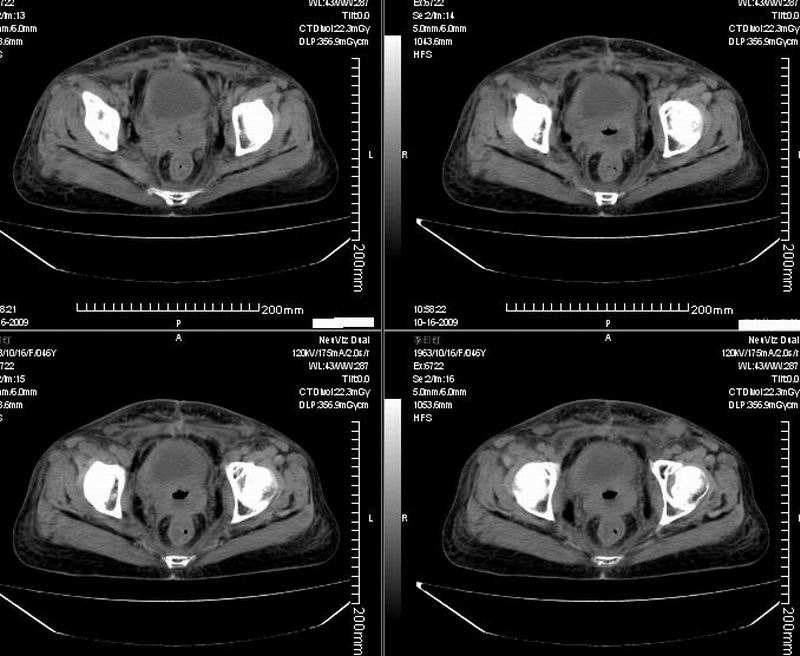

女:46y:一年前宫颈癌术后,现右下腹抚及肿块。

考虑宫颈癌术后复发周边侵犯/右中下腹及双侧腹股沟淋巴结转移。